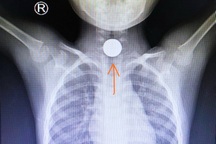

Ảnh minh họa.